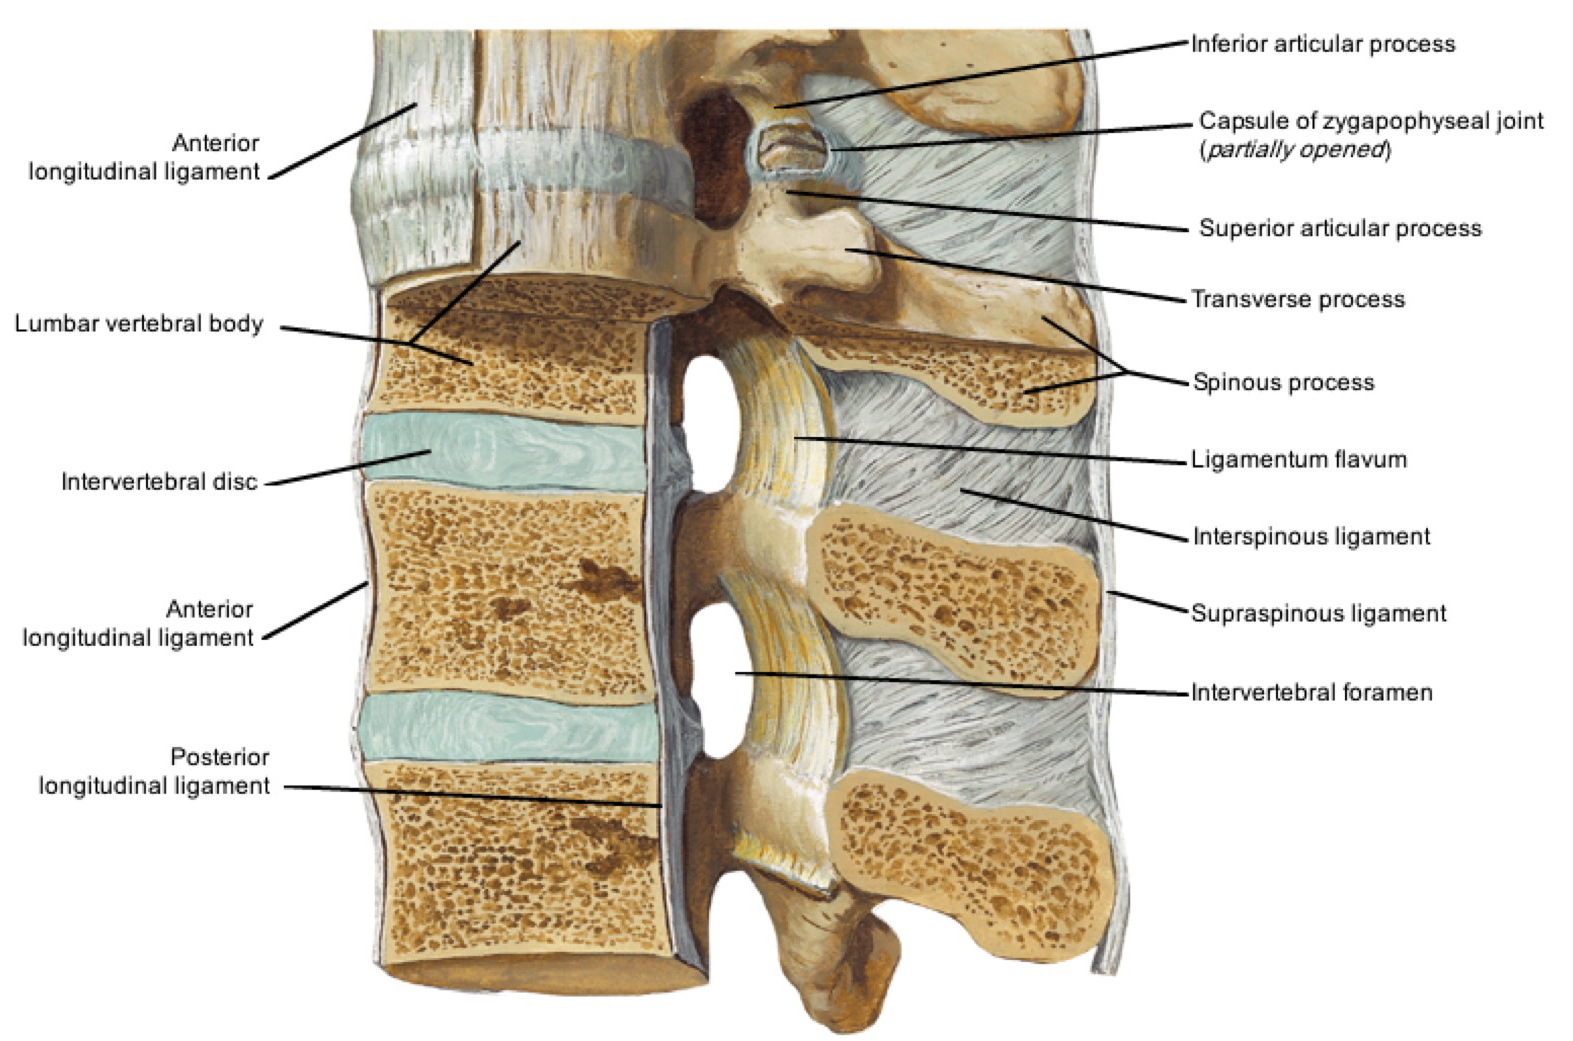

Anatomy of the vertebral column and spinal cord (Chapter 55) - Essential Clinical Anesthesia Review

The vertebral column usually contains three curves. The cervical and lumbar curves are convex anteriorly, and the thoracic curve is convex posteriorly. These curves, together with gravity, barricity of the local anesthetic,